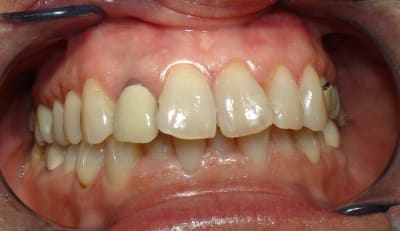

le hasard fait parfois bien les choses...patient revu ce matin pour une "bricole" sur une restauration postérieure...

il est intéressant de voir la maturation des tissus mous...et en plus VS des différences au niveau de l'hygiène, pas mal secteur 2 mais perfectible secteur 1...

ici on est à 3 mois post pose prothèses d'usage...la photo, prise un peu décalée, donne l'impression d'une différence de hauteur des collets, mais il n'en est rien (ou alors très peu...)

quand même content du résultat...;-) même si j'ai (lourdement)insisté pour que l'hygiène soit un peu mieux suivie...